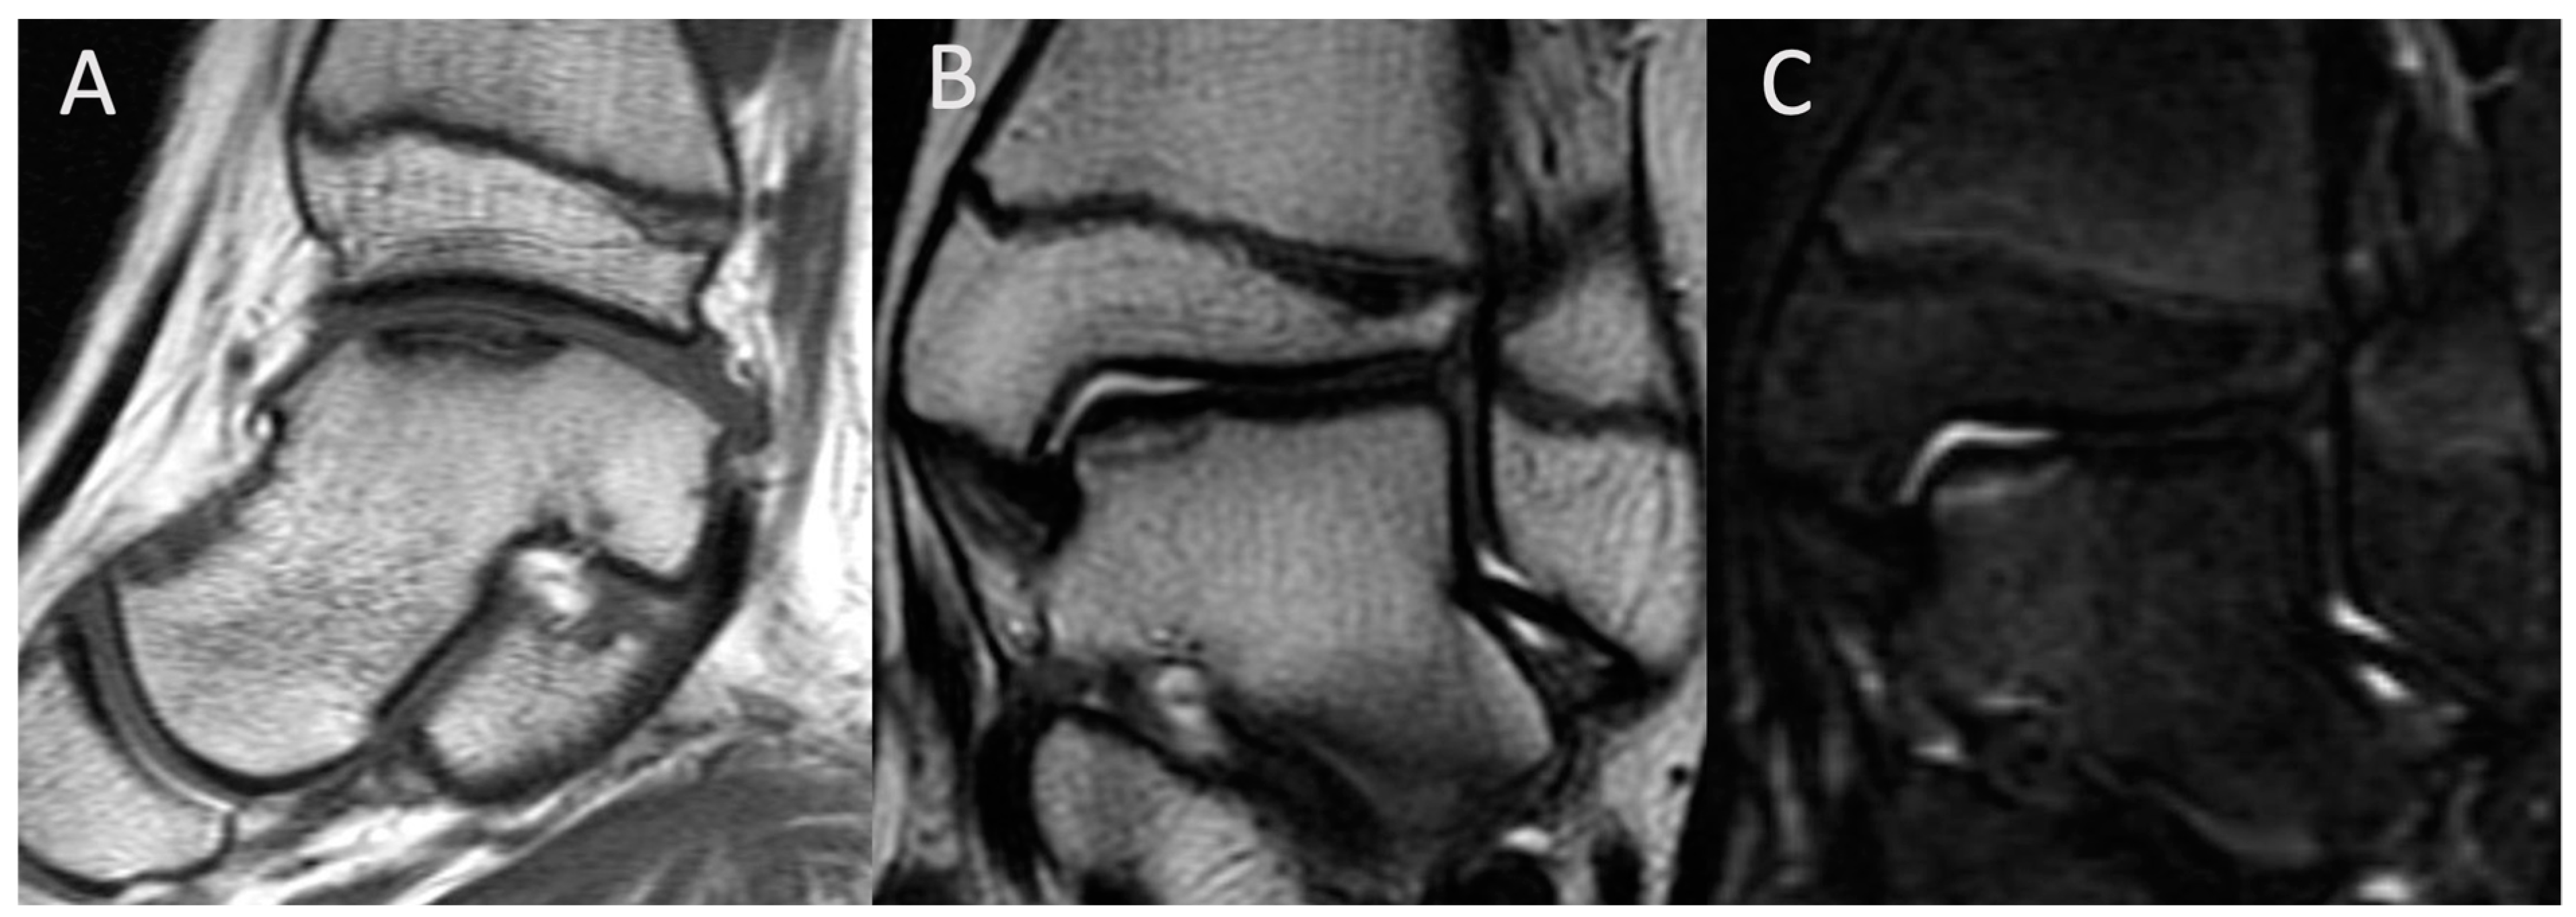

| MRI features | T1-weighted images display a single-density, low-signal intensity line. T2-weighted images display a high-intensity line with early necrotic-viable bone interface. | In T1-weighted images, the progeny is typically hypointense. In T2-weighted images, the progeny is mostly heterogeneous; this sequence can assess the integrity of articular cartilage, reactive marrow edema in the parent bone, and fluid or cystic changes at the parent-progeny interface. |